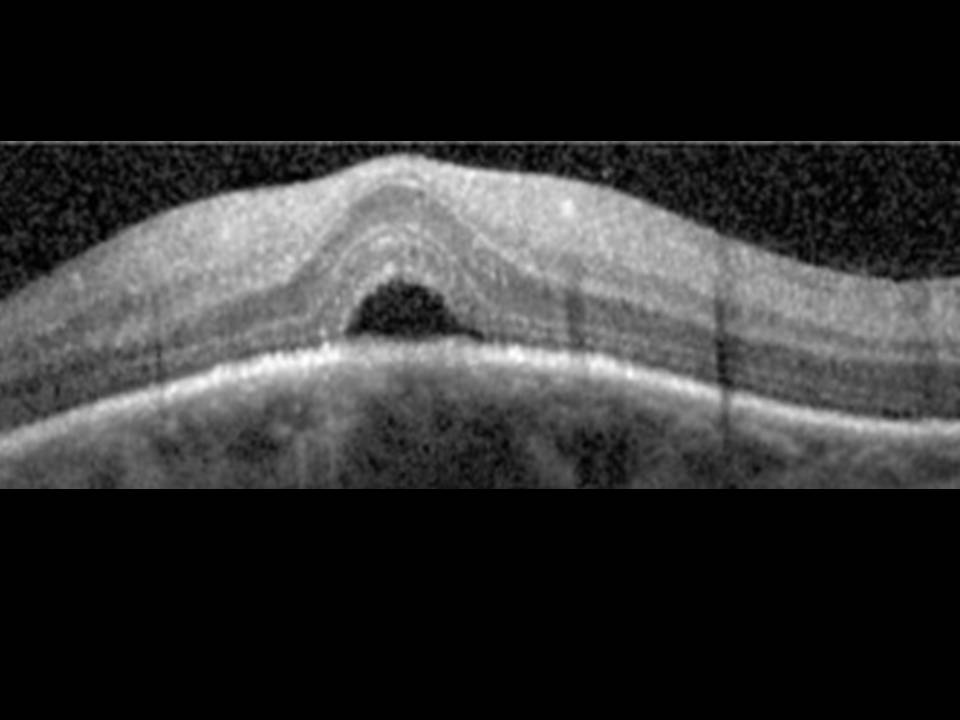

A miopia patológica é uma causa importante de cegueira, com prevalência crescente nos países desenvolvidos e em idades progressivamente mais jovens. É-lhe tradicionalmente atribuída uma forte componente genética, reconhecendo-se hoje fatores ambientais que podem limitar a sua progressão. Embora em muitos casos o agravamento da acuidade visual fosse atribuído à presença de neovascularização coroideia, descolamento de retina ou desenvolvimento de buraco macular, noutros esta progressão permanece por explicar. Novas técnicas de tomografia por coerência óptica permitiram recentemente a descoberta de entidades patológicas relacionadas com a maculopatia miópica, que abrem portas ao avanço na compreensão fisiopatológica da doença e na sua abordagem terapêutica, particularmente cirúrgica. Salientam-se os fenómenos de foveosquisis miópica, cavitação intracoroideia, tração vítrea paravascular (com formação de quistos, micropregas e defeitos lamelares) e fenómenos de distorção macular que revemos neste trabalho.